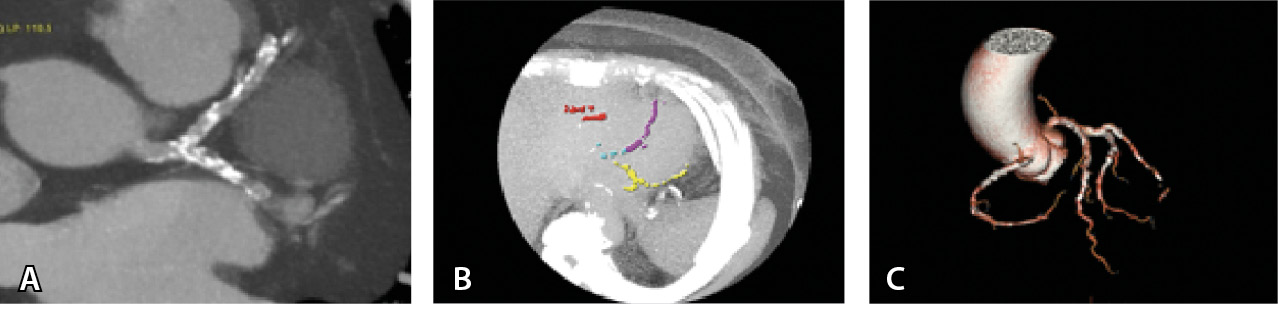

Больному проведена мультиспиральная компьютерная томография с ЭКГ-синхронизацией от бифуркации трахеи до верхушки сердца, с подсчетом индекса коронарного кальция (количественная оценка показателя Агатстона) (рис. 6). Заключение: индекс коронарного кальция 2242, свидетельствующий о выраженном кальцинозе коронарных артерий.

Рис. 6. Мультиспиральная компьютерная томограмма пациента Т., кальциноз коронарных артерий: А – мультипланарная реконструкция, массивные кальцинированные бляшки в передней межжелудочковой и огибающей артериях; Б, В – 3D-реконструкция, кальцинированные бляшки в левой и правой коронарных артериях